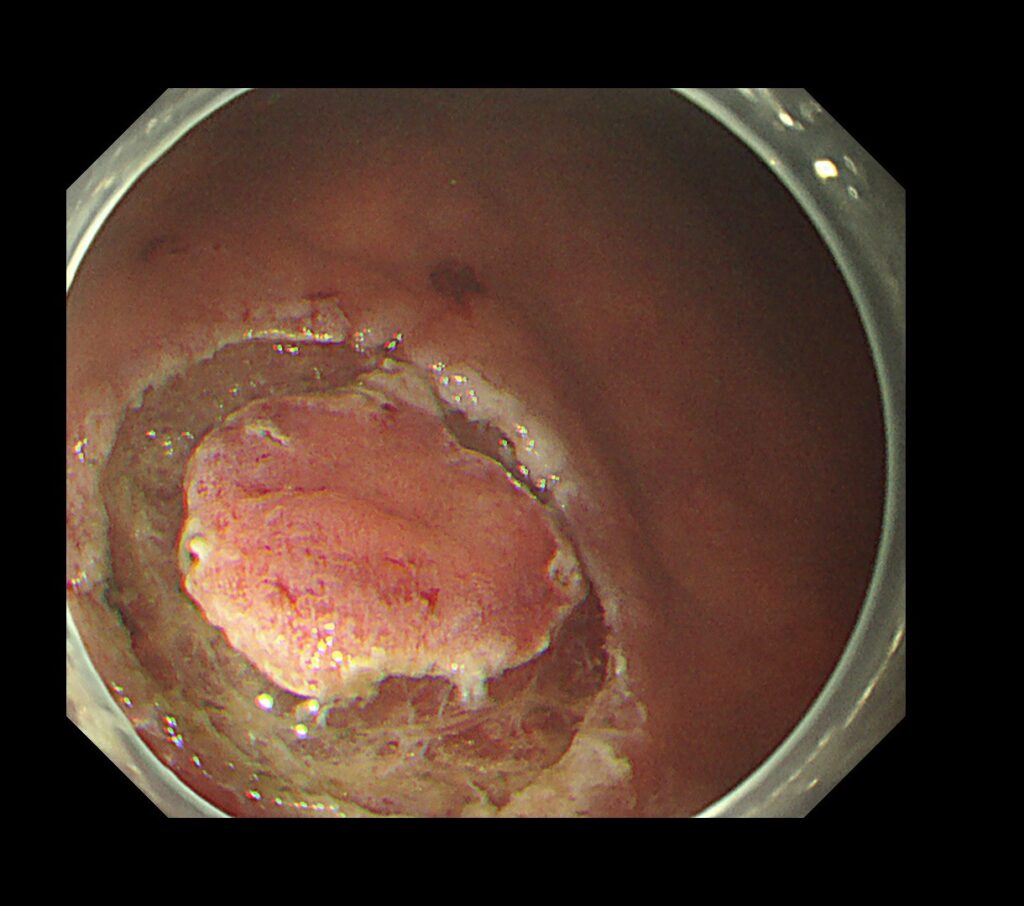

電気メスでマーキングをして、わずか5分で内視鏡治療終了しております。

内視鏡治療エキスパートのクリニックであれば、胃癌の内視鏡治療(ESD)は入院せず、日帰り治療の時代が到来したと考えております。